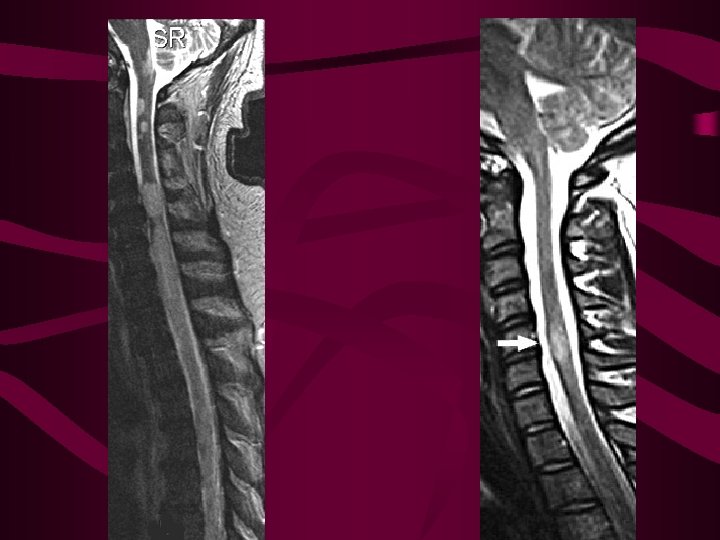

Espondilosis cervical con mielopatía • La causa más frecuente de mielopatía • Enfermedad degenerativa de la que afecta a las últimas vértebras cervicales • Clínica: 1) dolor y rigidez de cuello; 2) braquialgia, 3) debilidad espástica + ataxia • Patogenia : el mecanismo de daño medular parece ser la simple compresión. • Tratamiento: collarín o cirugía

Siringomielia • Dilatación cavitada de la ME que puede producir una mielopatía progresiva • Aparece región cervical baja y dorsal alta • En más de ½ de casos se asocia a Chiari • Etiopatogenia: alteración del flujo normal de LCR desde el IV ventrículo al espacio subaracnoideo • Hay casos de SR adquirida, se pueden producir por traumatismos, mielopatías inflamatorias, aracnoiditis crónica secundaria a tuberculosis u otras enfermedades, o a tumores intramedulares.

Siringomielia-Siringobulbia • Síndrome centromedular: déficit de la sensibilidad disociado y pérdida de fuerza y arreflexia en ES • Sensibilidad termoalgésica se pierde con una distribución “suspendida” en forma de capa, sobre la nuca, hombros y parte superior de los brazos, o manos. Vibratoria y posicional están conservadas • A medida que la cavidad aumenta de tamaño aparece espasticidad de EI, disfunción vesical o intestinal y en algunos casos síndrome de Horner. • Siringobulbia : parálisis del paladar o cuerdas vocales, disartria, vértigo o amiotrofia de lengua.

Siringomielia • Diagnóstico: Mediante RM, en todos los casos debe obtenerse RM encefálica y ME para ver si existe hidrocefalia y delimitar por completo la lesión • Si no hay malformación de Chiari debe hacerse RM contraste para descartar tumor medular • Tratamiento: quirúrgico, descomprimir la fosa posterior, si hay hidrocefalia derivarla. Si hay tumor, además habrá que resecarlo.